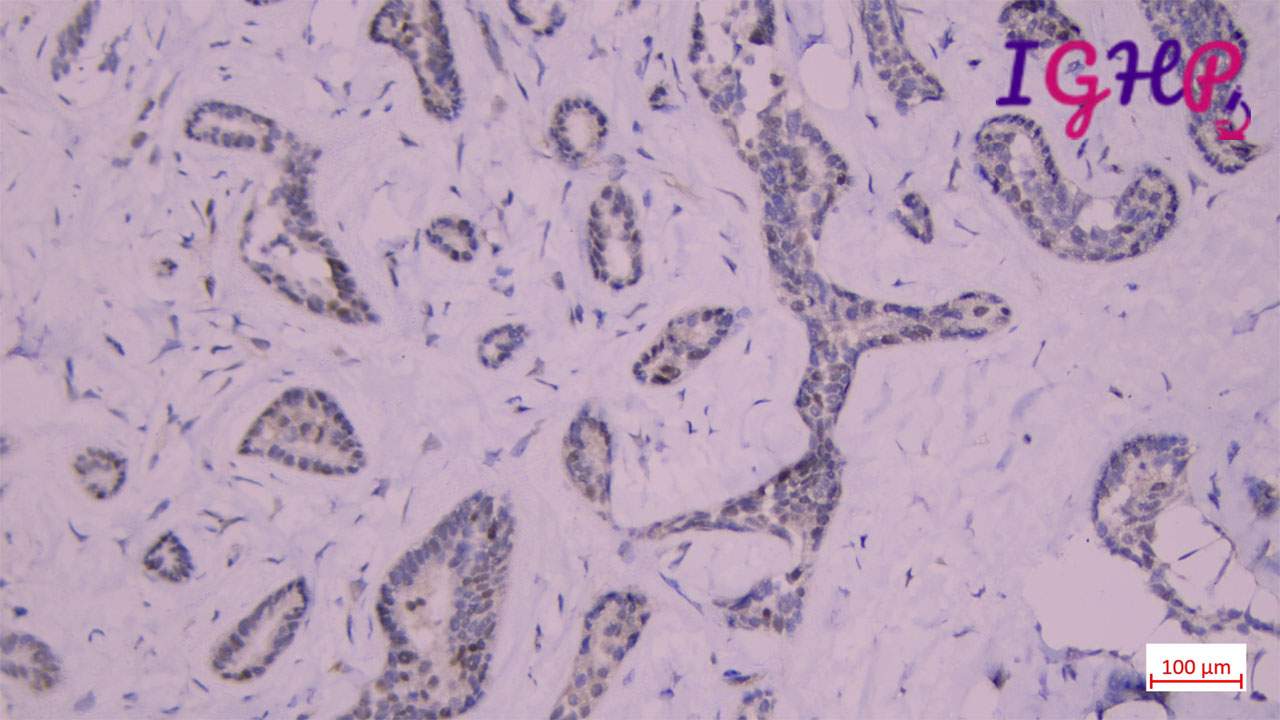

Microscopic Images-

Microscopic examination showed atypical bile ductular proliferation in dense sclerotic stroma. Areas of mild nuclear pleomorphism noted. Intraluminal apoptotic debris seen.

Immunohistochemistry Performed-

IHC performed for CK7, KI67 and P53